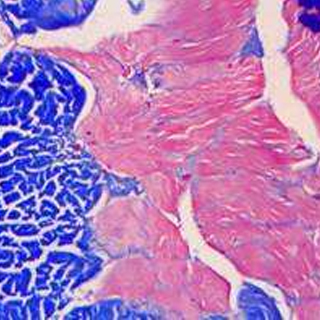

油紅0脂肪染色法是指在日常病理診斷和科研工作中為了顯示組織內的脂肪常采用油紅0進行染色的方法,油紅0為脂溶性染料,在脂肪內能高度溶解,可特異性的使組織內甘油三酯等中性脂肪著色。

正常情況下,除脂肪細胞外其他細胞內-般不見或僅見少量脂滴。在病理狀態下如這些細胞中出現脂滴或脂滴明顯增多,特別是在心、肝.腎等實質器官發生脂肪變性時,胞漿內出現大小不一的空泡, 這時常需鑒別空泡性質,用脂肪染色來區分是脂肪變性還是水樣變性或糖原貯留。在動脈粥樣硬化時,內皮細胞下的脂質沉著,用脂肪染色能將脂質清晰地顯示出來。由脂肪組織病變所弓|起的脂肪栓塞可用脂肪染色顯示栓子內的脂質,從而確診脂肪栓塞。用于腫瘤組織的鑒別診斷,由脂肪組織所發生的腫瘤在與其他組織來源的腫瘤相區分時,可以借助脂肪染色,脂肪組織所發生的腫瘤,脂肪染色為陽性。并可根據所顯示的細胞形態特點與類似腫瘤進行鑒別,腎透明細胞癌與腎上腺瘤,卵巢纖維瘤與卵泡膜細胞瘤。皮脂腺瘤與鱗狀細胞癌的鑒別診斷有意義。

實驗結果:

脂滴呈橘紅色至鮮紅色:細胞核呈深藍色。